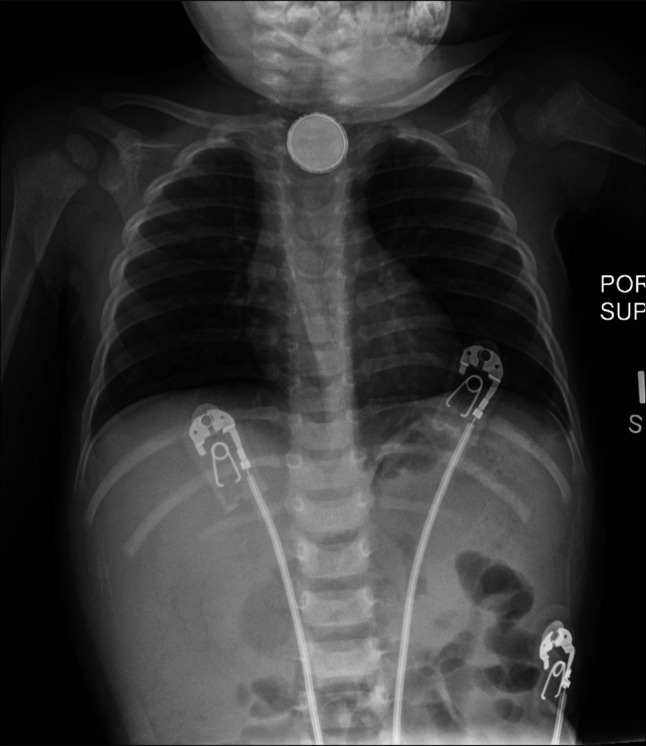

纽扣电池误食是小儿异物急诊的重要原因,往往会导致严重的并发症。我们提出的情况下,一个婴儿谁发展左总颈动脉食管瘘后纽扣电池摄入,这是进一步复杂的假性动脉瘤的形成。通过随访影像确诊,假性动脉瘤成功使用分流支架治疗。患者保持临床稳定,无神经功能障碍。这一病例强调了早期诊断和干预对预防出血和中风等危及生命的并发症至关重要。此外,它强调了随访影像学研究的必要性,即使在无症状的患者中,也可以监测延迟并发症并告知正在进行的治疗。

Button battery ingestion is a significant cause of pediatric foreign body emergencies, often leading to severe complications. We present the case of an infant who developed a left common carotid-esophageal fistula after button battery ingestion, which was further complicated by the formation of a pseudoaneurysm. The diagnosis was confirmed through follow-up imaging, and the pseudoaneurysm was successfully treated using a flow diversion stent. The patient remained clinically stable without neurological deficits. This case underscores the critical importance of early diagnosis and intervention to prevent life-threatening complications such as hemorrhage and stroke. In addition, it highlights the necessity of follow-up imaging studies, even in asymptomatic patients, to monitor for delayed complications and inform ongoing management.